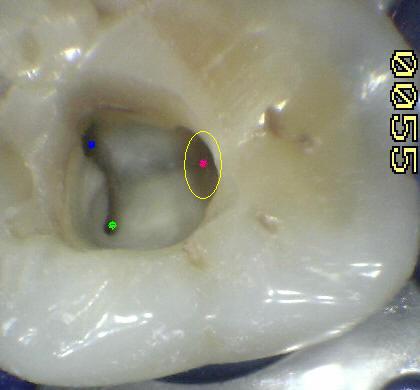

El conducto y el orificio es esencialmente un agujero en la raíz, la transmisión de luz  muestra al orificio de entrada del conducto como una mancha oscura en un fondo brillante. Ver imagen izquierda superior, la siguiente imagen es el resultado de utilizar una cámara intraoral, con 10 aumentos (X10)

El poder de magnificación del MO con visión indirecta y luz coaxial permite localizar las entradas de los conductos calcificados. Incluso los más pequeños y difíciles de ver como el conducto mesio-palatino (Ver flecha amarilla imagen superior izquierda)

La flecha amarilla indica un posible cuarto conducto. Debe abrir hacia mesial  para eliminar la pared marcada en un circulo celeste, a la misma profundidad que el conducto mesio-vestibular.  Ver imagen derecha.